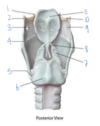

Which muscle is labeled by #1?

What is its action?

Aryepiglottic muscle

Pulls the epiglottis posteriorly to help close the larynx - opposes the thyroepiglottic muscle

(Restricts the opening like a purse string, but doesn’t close it completely)

Which structure is labeled by #5?

What is its action?

Cricothyroid muscle

Phonation - Tilts the thyroid forward to tense the vocal cords -> higher pitches

Innervated by the external laryngeal nerve

Which structure is labeled by #3?

Lateral cricoarytenoid muscles

(Adduct/close the vocal cords)

Which structure is labeled by #5?

What is its action?

Posterior cricoarytenoid muscle

Abducts vocal cords -> opens airway

Which fold is labeled by #2?

Vestibular fold (aka false vocal fold)